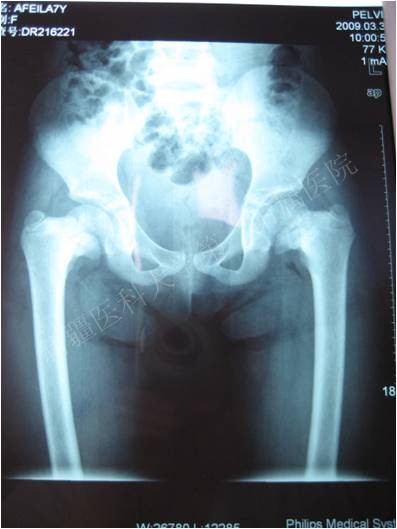

一典型患者术前术后X线片